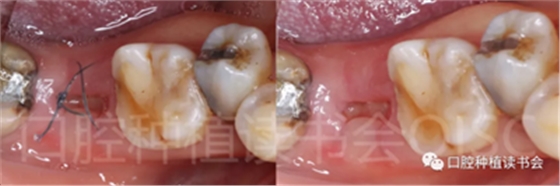

5.3.7 術(shù)后1周拆線,47位點(diǎn)愈合良好(圖20),患者術(shù)后未訴疼痛不適。

圖20 不翻瓣即刻種植手術(shù)可有效減小術(shù)后不適。

5.3.8 術(shù)后第3周,拔除48近中傾斜阻生智齒,觀察47位點(diǎn)愈合良好(圖21)。

圖21 拔除傾斜阻生的48,利于47后期的修復(fù)。